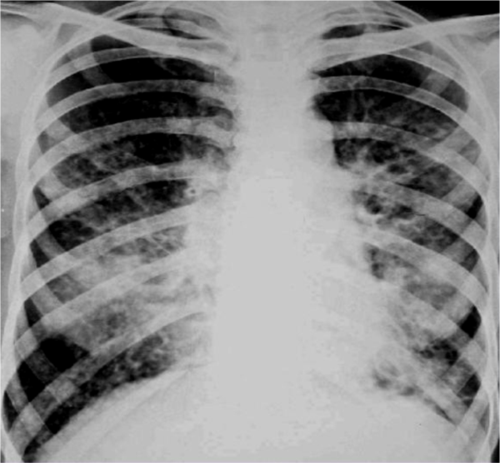

2.小叶性肺炎 表现为肺纹理增多,模糊.

小叶性肺炎表现为沿肺纹理分布的斑片状模糊致密影,密度不均,多发

有些病例具有支气管肺炎,即小叶性肺炎的特点.

小叶性肺炎的x线表现

小叶性肺炎x线

小叶性肺炎x线图片

小叶性肺炎胸片